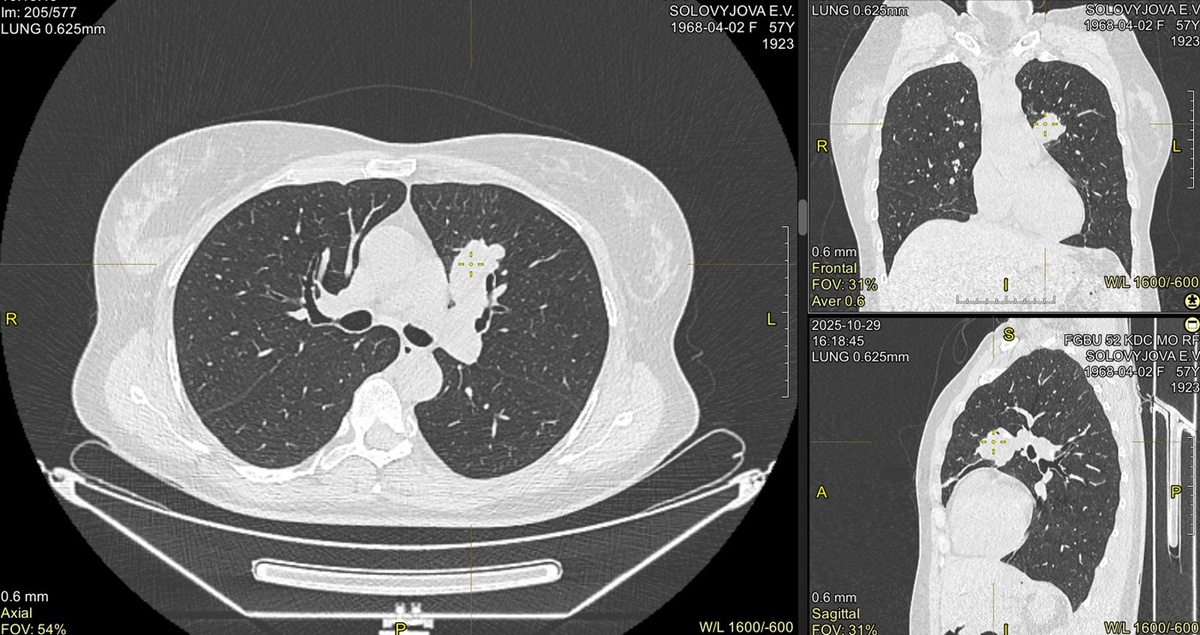

На первичную консультацию пришла пациентка с новым образованием в корне левого лёгкого. Было только заключение КТ – отправили на ПЭТ-КТ: нашли один активный очаг (SUV≈13), больше ничего, лимфоузлы средостения без накопления.

Но ровные контуры насторожили – решили выполнить трансторакальную биопсию под КТ-контролем.